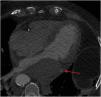

This is the case of an 80-year-old man with multiple cardiovascular risk factors admitted to the intensive care unit due to non-ST-segment elevation acute myocardial infarction. The coronary angiography performed reveals the presence of left main coronary artery and left anterior descending coronary artery disease. Revascularization is attempted through overlapping drug-eluting stent implantation (Fig. 1, blue arrow). Afterwards, the left circumflex artery is crossed with a guidewire (Fig. 1, red arrow). Procedure is uneventful. However, suddenly after the procedure the patient shows signs of heart failure. Transthoracic echocardiography confirms the presence of a 64mm×40mm mass—echolucent inside—with demarcated borders at left atrium lower level with a reduced size of such cavity compromising atrial filling consistent with left atrial wall hematoma (Fig. 2).